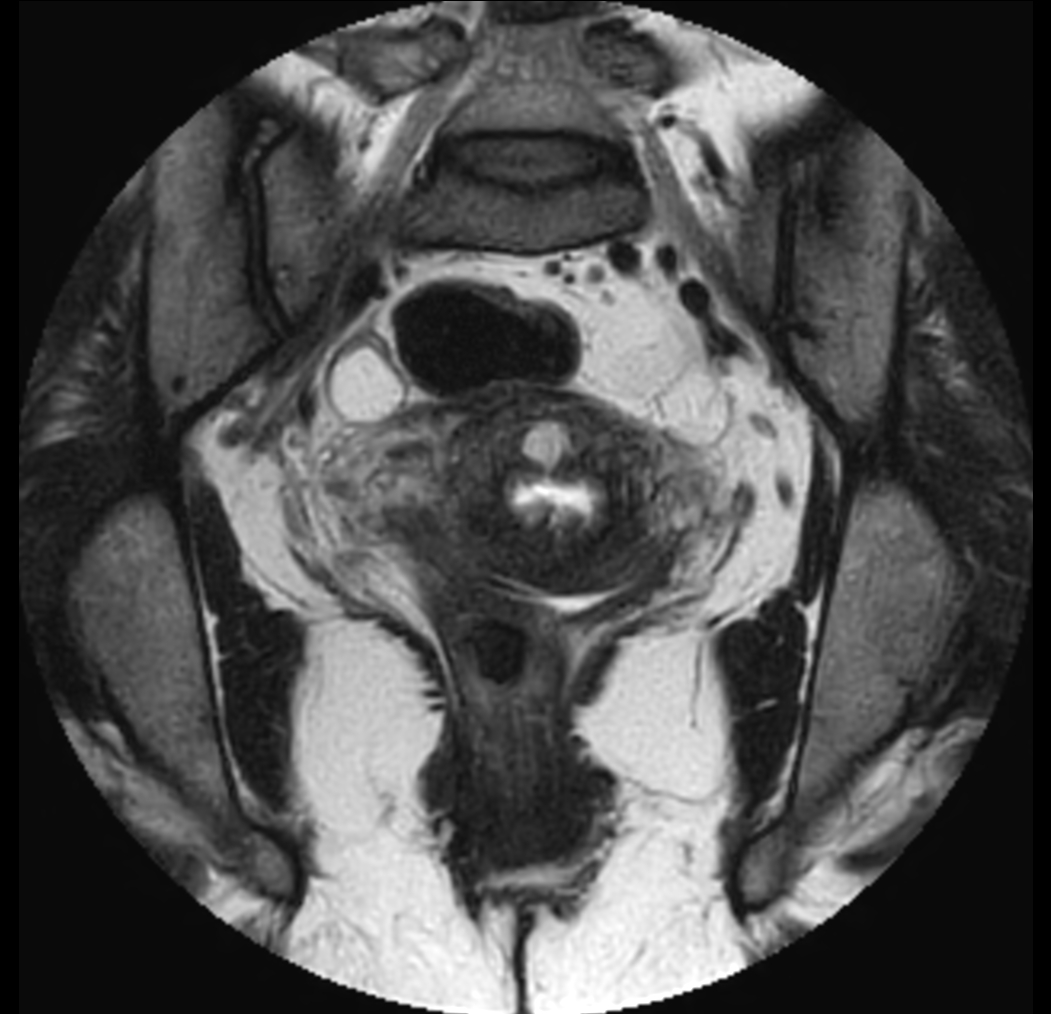

Coronal MultiVane XD - T2w TSE